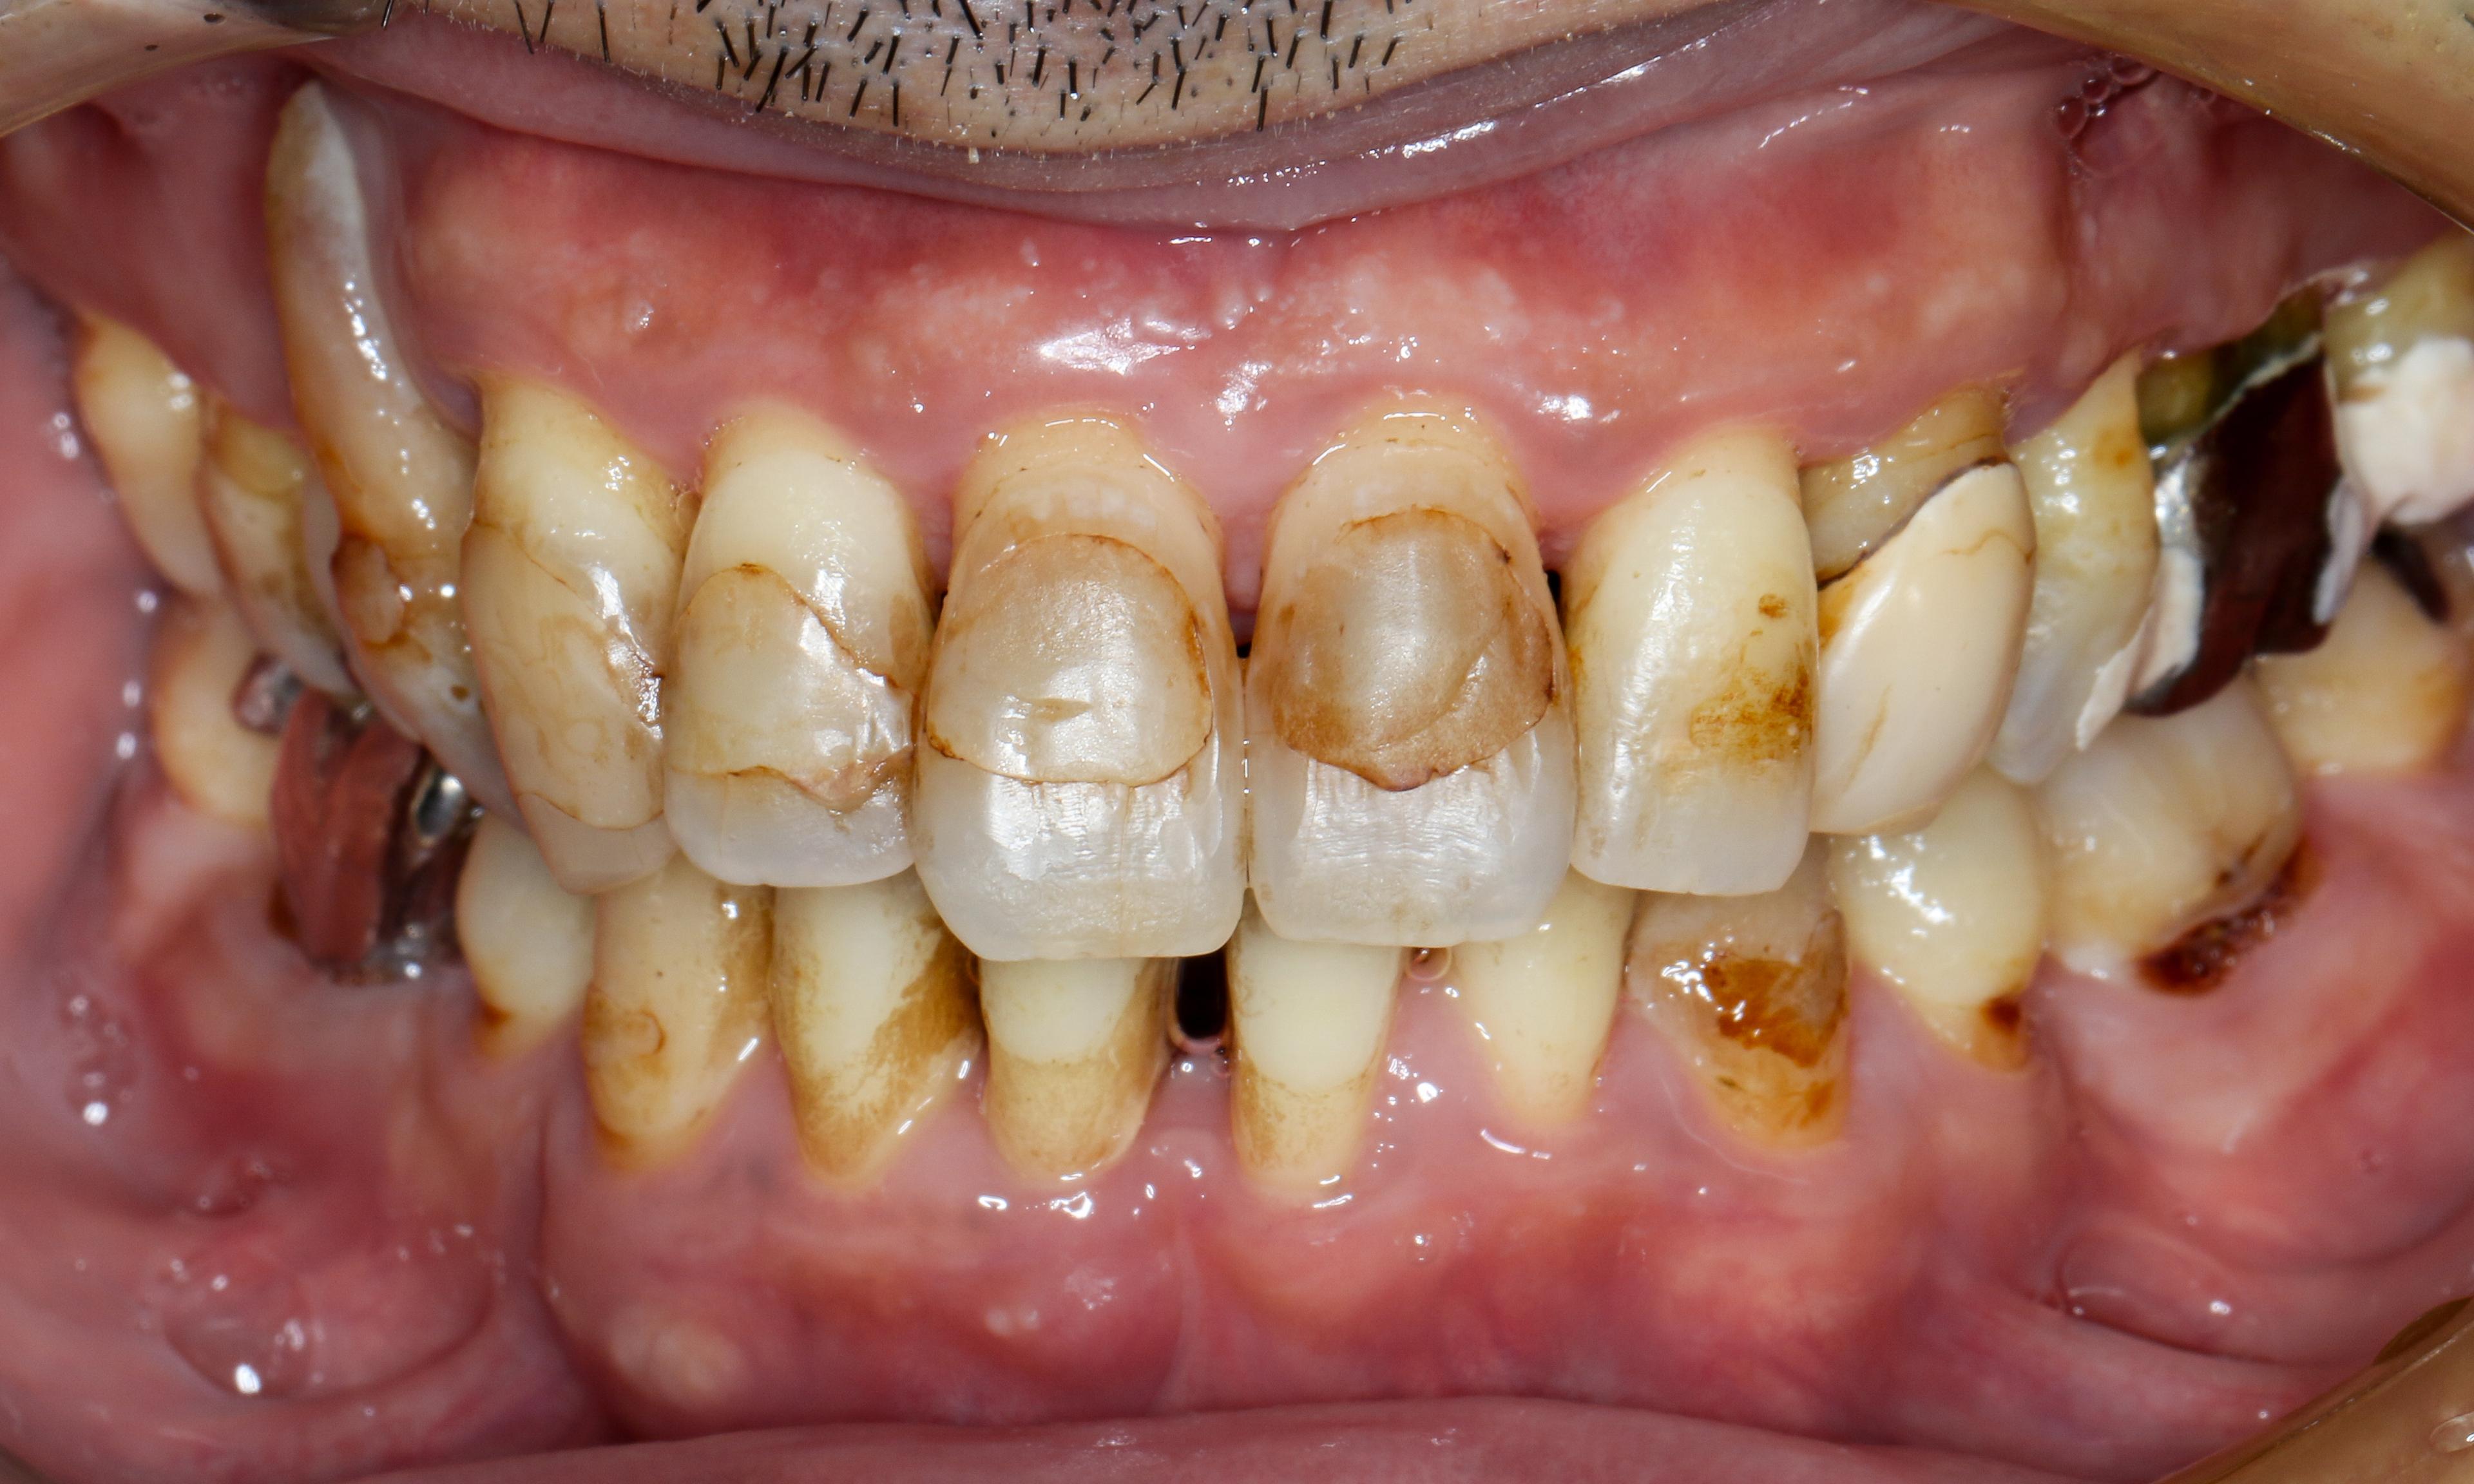

歯茎の腫れも治まり健康な歯肉の色になってきている。

初診時の状態。差は歴然。

初診時と比べて歯周ポケット深さは6mmまで改善し、歯周組織再生療法により抜歯を回避できると判断できるまで回復をしています。